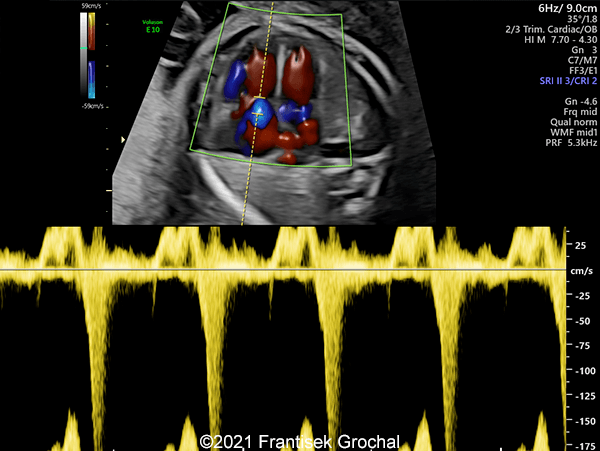

Case Report: A 24-year-old secundigravida, primipara presented to our office at 24 weeks and 6 days of her pregnancy due to a right-sided cranial parieto-occipital mass of the fetus. We obtained the following images.

Our ultrasound images at 24 weeks, 6 days show a highly vascularized, mostly solid mass measuring 58 x 45 x 34mm in the right-parieto-occipital subcutaneous region. Vascular supply of the lesion could be traced to the right vertebral artery. Repeat ultrasound exams done later in pregnancy demonstrated that the size of the mass remained stable with overall mass volume about 58 cm³.